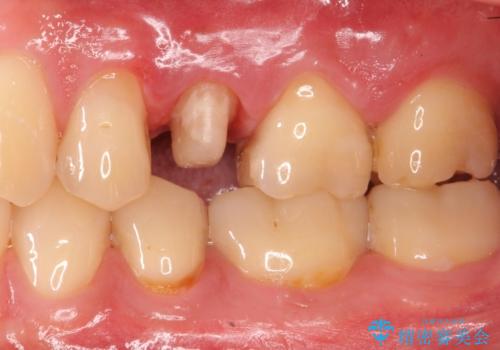

- 左上の歯茎にできものができたとのことで来院された患者様です。

術前検査より根管内の感染が疑われたため、再根管治療を行います。

根管内の感染源を可能な限り除去し洗浄しました。

術後は腫れがなくなり特に症状も出ず、メンテナンスに移行しました。